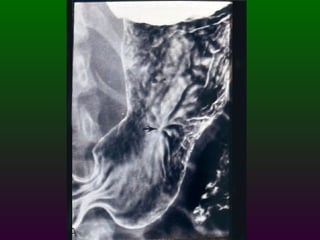

SEGD PATOLOGÌA ESOFÀGICA D.- INFLAMACIÓN: Esofagitis péptica por reflujo Esofagitis por radiación Esofagitis medicamentosa Esofagitis cáustica

SEGD PATOLOGÌA ESOFÀGICAD.- INFLAMACIÓN: Esofagitis péptica por reflujo Esofagitis por radiación Esofagitis medicamentosa Esofagitis cáustica